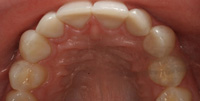

Lingual Veneers - Why? To restore worn-away enamel from acid erosion due to eating disorders.Lingual veneers are veneers that are placed on the inside, or lingual, surface of the front teeth. Rather than remove any healthy enamel from the remaining front and back sides of the teeth to do crowns, lingual veneers offer a conservative alternative for those who have experienced acid erosion, or tooth wear, of the lingual surfaces due to the detrimental effects of eating disorders such as bulimia. The goal is to build up and restore worn away teeth while preserving as much of the natural, beautiful and healthy tooth structure as possible. This strengthens and reinforces the tooth from further damage and drastically reduces sensitivity so a healthy diet and lifestyle can be resumed. Professional dental help for bulimia It is important to seek dental care if you have bulimia and to openly share with the dentist what is happening. Many dentists are caring professional people who understand the problems with bulimia and want to help. Without the dentist's help, the dental consequences of your bulimia can be severe. Dr. Berland can usually provide all of the dental services needed to restore the bulimic patient back to good dental health in a confidential and private manner. Additionally, Dr. Berland can help a bulimic patient manage the condition so that, even if they are continuing to have problems, the dental consequences of bulimia are lessened or eliminated. The Dallas Dental Arts services can be specially arranged for a bulimic patient so that all needed dental treatment can be intensively completed in a short period of time. This makes it possible for patients from out of town to complete their desperately needed dental care confidentially and in as few visits as possible. The Dallas Dental Arts can also assist in obtaining the funds for this care so everything that needs to be done can be completed. For more information on financial assistance, please click here. Dr. Berland has successfully cared for many patients suffering from bulimia and would be pleased to meet with you in a confidential consultation. Here, You can privately discuss your choices in dealing with your bulimia. Dr. Berland understands that you are struggling with bulimia and that it may take time to deal with the consequences of your bulimia. Privately speaking with Dr. Berland can be your first step in conquering your bulimia. Please consider calling (214)999-0110 and scheduling a consultation. You do not have to say why you are visiting, just that you would like a private consultation. If calling for an appointment is too embarrassing, you can first email Dr. Berland at drberland@dallasdentalspa.com or you can schedule a consultation and privately email him to let Dr. Berland know that you wish to talk about your bulimia. This young lady came to our office looking for a way to improve her smile, self-image and most importantly, her health. As a recovering bulimic patient, she had endured years of damage to her enamel from her previous history of eating disorders. In her case, the erosion wore all the way through her enamel and even into the soft, sensitive inner tooth layer, the dentin. She sought us out to find a way to restore her smile without further compromising the fragile condition of her teeth. Other dentists discussed filing her already thinned down teeth further and "strengthening" them with porcelain crowns. Our approach was completely different. Why take away more when you don’t have much to begin with? We recommended she try lingual resin veneers (on the backside of her teeth) followed by cosmetic one-stop bonding on the front and especially the edges of her teeth. This is a completely noninvasive and a purely additive procedure. She would be adding strength to her teeth, fortifying them rather than removing any of her remaining enamel, thereby reinforcing her teeth, improving her dental condition and creating the beautiful, yet natural, smile she desired. When the patient heard of this conservative treatment alternative, it made sense to her to preserve her teeth to maintain her health and restore her smile. Not only were the back sides of her teeth built out, length was added to replace what was worn over the years for a more youthful smile. After the no-shots, no-drilling, and no-pain appointment, her teeth were no longer sensitive to sweets, hot or cold. The patient was very pleased with her results. She not only gained a beautiful, new smile, but she also had a renewed confidence in herself and a reassurance of a healthier smile – and that means a healthier lifestyle as well! With all the focus of the media on diets, exercise equipment and personal care products, people are more concerned with their appearance and physical health than ever. In an effort to meet today's standard of beauty and "health", many people are quick to try the newest crash diet fad without ever realizing that this may, in fact, be the incorrect way to diet. These crash dieters who excessively fast, or try every new trend, tend to have a lack of, or decrease in certain vitamins, most notably Vitamins D, B-12 and calcium. They also tend to lack certain minerals and proteins in their diets. These are very important vitamins especially for the health of the teeth and gums. What can occur is that dieters tend to have a diet high in fruits which may contain a high content of natural sugars. These sugars tend to decay and erode the enamel of the teeth. Mints, used to combat the bad breath associated from Ketosis caused by an unbalanced protein diet and "so-called" Power Bars can further decay the teeth. Dieters also tend to take diet pills that may cause a decrease in saliva flow as a side effect. This decrease in saliva flow tends to increase the acid levels in the mouth which may cause an increased level of cavity formation. Antidepressants and decongestants have the same effect. Dr. Berland cares about the health and well-being of his patients. If you are currently on a diet that restricts certain food groups and/or you are taking a supplement or prescription diet aid, your oral health may compromised and in need of attention. Click here to see an example of the effects of eating disorders on your teeth. Please discuss with Dr. Berland at your next appointment any of these changes in diet or methods of weight control and any problems or discomfort you may be experiencing in your teeth and gums. Dr. Berland has many conservative measures to prevent and alleviate these conditions. Preventing a dental situation before it becomes a problem can save not only your teeth-- but, discomfort, time, money and your health. |